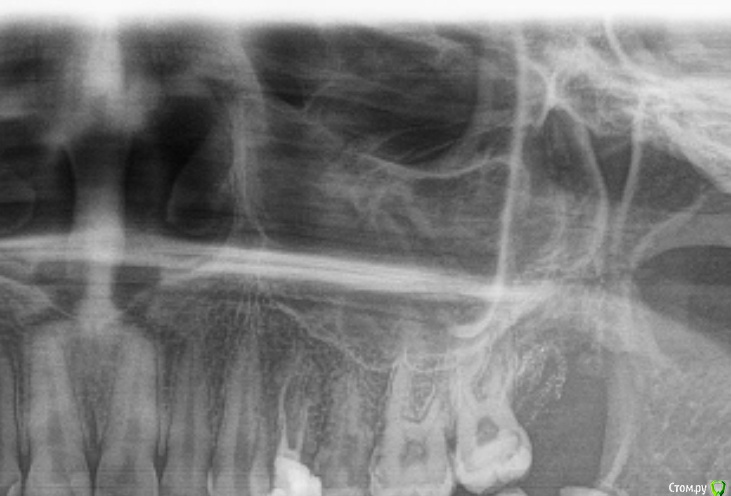

Marialalala Опубликовано 22 марта, 2020 Поделиться Опубликовано 22 марта, 2020 Здравствуйте, 4 дня назад удалили верхний зуб мудрости, удалили быстро сам зуб, но потом ещё вычищали отломившейся корень, по ходу делали несколько прицельных снимков, врач сказал, что все чисто, в конце была проведена «носо-ротовая» проба, оказалась перфорация, врач положил губку альвостаз и ушил лунку наглухо, выписал антибиотик, капли гормональные и т д, пришла на повторный осмотр через 2 дня, врач осмотрел лунку и сказал, что все хорошо и должно быть все хорошо, но если вдруг появятся симптомы... (одонтогенного гайморита), то конечно прийти к нему. Мне необходимо далее продолжать лечение зубов, поэтому как раз сегодня сделала панорамный снимок. Скажите, все ли хорошо в области удаленного зуба по снимку? Нет ли отломков зуба в пазухе, воспаления? Очень переживаю, так как есть знакомый, оказавшийся после удаления зуба в члх. Самочувствие хорошее, температуры нет, болевых ощущений нет. Два файла прикрепила - с зубом (того года ) и на 4 день после удаления Ссылка на комментарий

red_butler Опубликовано 22 марта, 2020 Поделиться Опубликовано 22 марта, 2020 нормально 2 Ссылка на комментарий